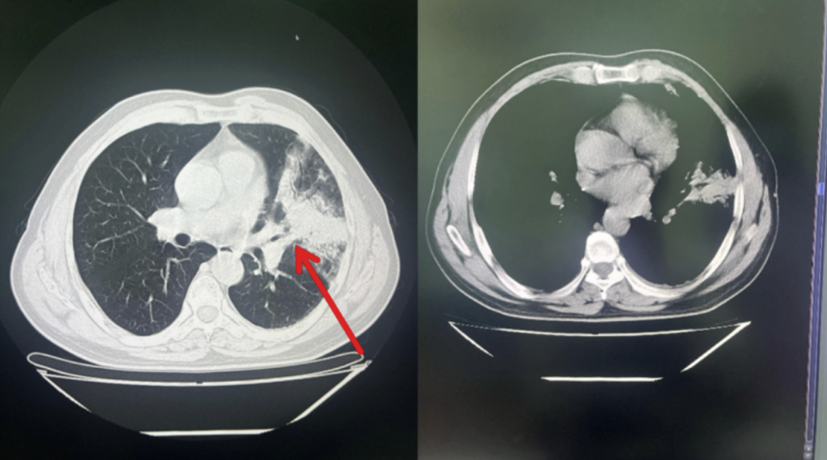

经上述方案治疗后,患者未再发热。复查血常规、CRP均恢复正常。胸部CT示左肺上叶病灶明显减小,左侧胸腔积液消失。病情好转达到出院标准,于9月20日出院。10月9日门诊复查,血常规:白细胞计数:5.49×109/L;中性粒细胞百分比:55.81%,C反应蛋白<5.0mg/L,PCT<0.05ng/ml。

胸部CT:左肺上叶病灶完全吸收。恢复良好。见图5:

图5:胸部CT扫描